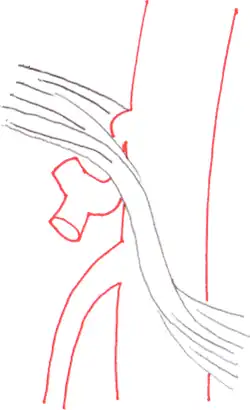

| Median arcuate ligament syndrome results from compression of the celiac artery by the median arcuate ligament. The median arcuate ligament is a fibrous arch formed by the left and right diaphragmatic crura, visible here on the underside of the diaphragm. | |

The median arcuate ligament is a ligament formed at the base of the diaphragm where the left and right diaphragmatic crura join near the 12th thoracic vertebra. This fibrous arch forms the anterior aspect of the aortic hiatus, through which the aorta, thoracic duct, and azygos vein pass. The median arcuate ligament usually comes into contact with the aorta above the branch point of the celiac artery. However, in up to one quarter of normal individuals, the median arcuate ligament passes in front of the celiac artery, compressing the celiac artery and nearby structures such as the celiac ganglia.[2] In some of these individuals, this compression is pathologic. It leads to the median arcuate ligament syndrome.[2]

Further evaluation and confirmation can be obtained via angiography to investigate the anatomy of the celiac artery.[5] Historically, conventional angiography was used, although this has been largely replaced by less invasive techniques such as computed tomography (CT) and magnetic resonance (MR) angiography.[2][5] Because it provides better visualization of intra-abdominal structures, CT angiography is preferred to MR angiography in this setting.[5] The findings of focal narrowing of the proximal celiac artery with poststenotic dilatation, indentation on the superior aspect of the celiac artery, and a hook-shaped contour of the celiac artery support a diagnosis of MALS.[2] These imaging features are exaggerated on expiration, even in normal asymptomatic individuals without the syndrome.[2]

Proximal celiac artery stenosis with poststenotic dilatation can be seen in other conditions affecting the celiac artery.[2] The hook-shaped contour of the celiac artery is characteristic of the anatomy in MALS and helps distinguish it from other causes of celiac artery stenosis such as atherosclerosis.[2] This hooked contour is not entirely specific for MALS however, given that 10–24% of normal asymptomatic individuals have this anatomy.[2]